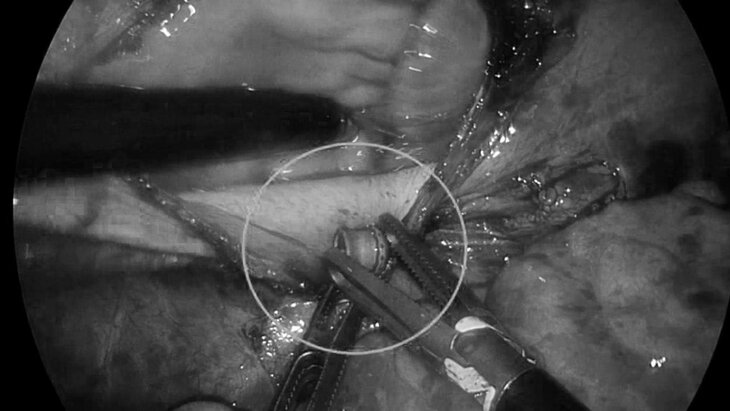

Подмосковные врачи извлекли пулю из сердца подростка

19 августа 2025